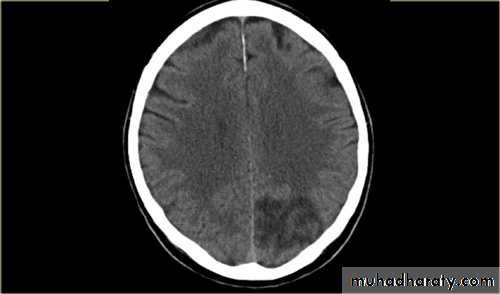

CT scan :-CT will be normal in early infarction (less than 6 hours).CT very sensitive for acute hemorrhage.